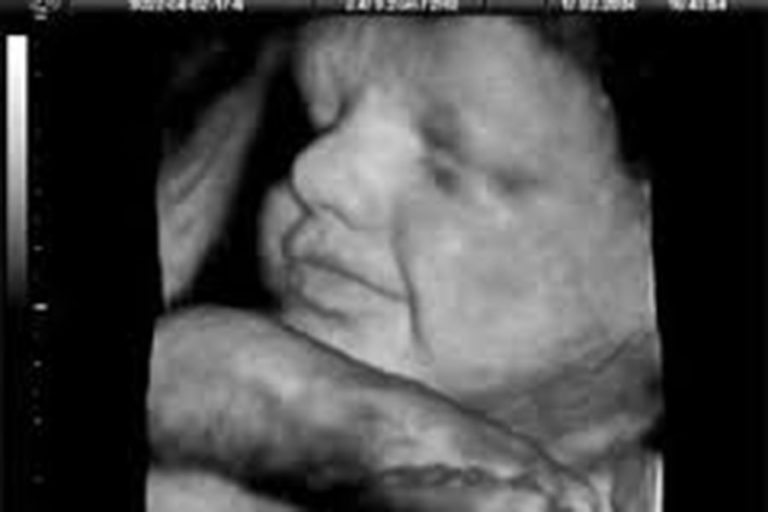

Drug Effects on the Fetus

Everything we eat and are exposed to has the potential of crossing the placental barrier. Illicit drugs are among substances that are correlated with fetal demise.

Still-born births

It is difficult to know exactly why a fetus dies in many cases. Find out more about causes and investigation of stillbirths here.